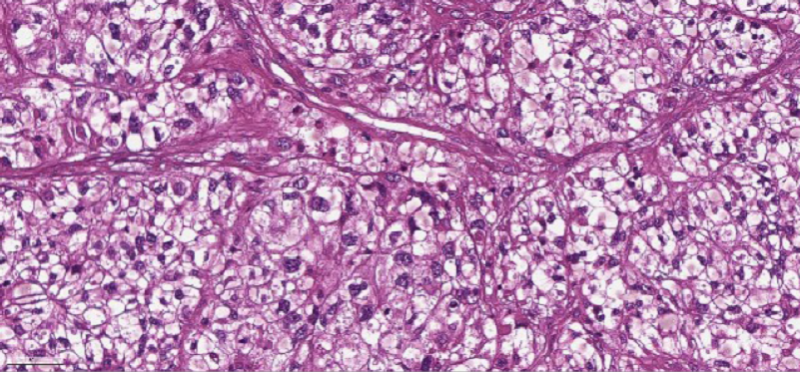

В 2007 году у мужчины была удалена почка по поводу онкологического заболевания. Однако через 10 лет были обнаружены метастазы в легких и левой бедренной кости. С помощью иммунотерапии удалось уменьшить очаги в легких, однако опухоль бедренной кости привела к ее патологическому перелому. На снимке видно густое сосудистое сплетение опухоли, которая прорасла в кость и стала причиной патологического перелома шейки бедра:

Результаты гистологического исследования удаленного фрагмента кости: «Микроскопически: метастазы светлоклеточного почечноклеточного рака. Макроскопически: в мягких тканях определяется опухоль размерами 5.4 / 3.4 / 4 см белесоватого цвета с врастанием в кость на 1,5 см Расстояние до края резекции кости 3,5 см». То есть подтверждается, что источник метастаза — удаленная ранее почка, а место отпила выбрано правильно. Хирург прислал изображение клеток опухоли: